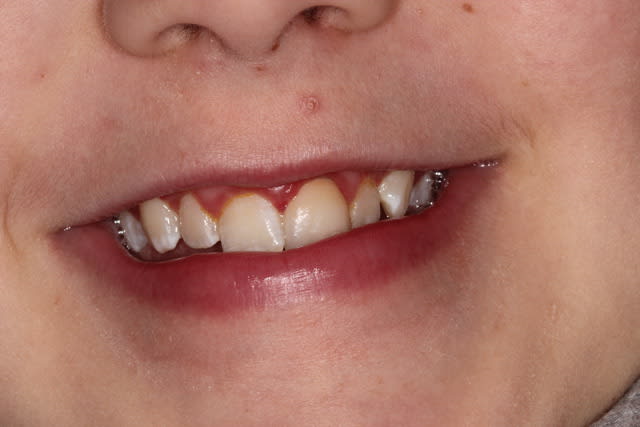

Petit patient de 9 ans vu il y a un an et demi. Patient hyperactif, un peu casse cou. Fracture enamelodentinaire sur 21.

Réparation au composite qui s'est cassée la figure au bout de quelques semaines. Je l'ai refaite, mais rebelote. Au bout de plusieurs echecs du composite j'ai décidé de tenter une facette céramique malgré :

- l'absence de maturité parodontale

- l'odf à faire

- l'hygiene moyenne

- et c'était seulement mon deuxieme cas de facette dans ma jeune carriere...

Bref, je l'ai revu ce matin, un an aprés la pose de la facette. Ca a tenu (heureusement...) et c'est pas trop vilain, même si on peut critiquer les caractérisations de la ceramique.